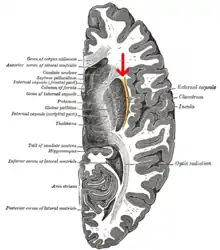

Vue supérieure d'une coupe horizontale d'une dissection profonde des ventricules du cerveau et des ganglions de la base.

La capsule externe (en latin : capsula externa) est un ensemble de tractus de fibres de substance blanche dans le cerveau (formées des axones). Ces fibres passent entre le segment le plus latéral (c'est-à-dire vers le côté de la tête) du noyau lenticulaire (plus précisément le putamen) et le claustrum (appelé également l'avant-mur)[1].

La substance blanche de la capsule externe contient des fibres connues par les fibres d'association (en) corticocorticales, ces fibres sont responsables de relier le cortex cérébral avec une autre aire corticale. La capsule elle-même apparaît comme une mince feuille blanche de substance blanche[2].

Le putamen sépare la capsule externe de la capsule interne médialement et le claustrum la sépare de la capsule extrême latéralement. Cependant, la capsule externe rejoint éventuellement la capsule interne autour du noyau lenticulaire.